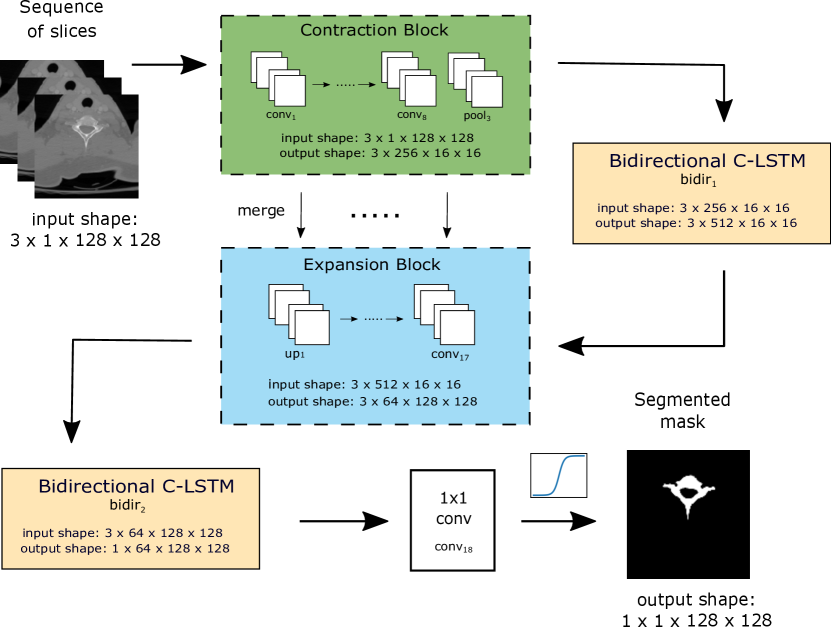

Fig. 1 shows the high-level overview of the proposed architecture on a sample sequence of vertebrae slices. Table I complements the figure with tensor shapes for each layer for a particular case when the length of input sequences is equal to three.

As mentioned previously, the network takes an odd-lengthed spatial context as the input. This sequence is then passed to the contraction block (green in Fig. 1 and the corresponding layers from to in Table I). As all convolutional and max pooling layers are enclosed into a time-distributed wrapper, each element of the sequence is processed through the contraction block independently.

In order to capture spatio-temporal correlations between slices the features extracted for each element of the input sequence are passed into the C-LSTM block [2] at the end of the contraction part (layer in Table I). In order to enable the network to learn spatio-temporal correlations of the slices in both directions, we used a bidirectional extension for the C-LSTM with the summation operator combining forward and backward outputs. This C-LSTM block aims at adding the explicit dependency of the low-dimensional high abstract features extracted for the elements of the sequence.

The sequence output of the bidirectional C-LSTM block is then passed to the expansion part (blue in Fig. 1 and the corresponding layers from to in Table I). Similarly to the contraction part, each element of the sequence is processed independently via time-distributed convolutional as well as upsampling layers. After every upsampling layer, the features are concatenated with the corresponding features from the contraction part. When the spatial resolution of the features reaches the desired output sizes, the sequence is passed to another bidirectional C-LSTM block (layer in Table I). The sequence is processed in both directions and the outputs are combined by summation. At this stage this block contributes towards two goals: adding explicit dependency for the high-dimensional high-abstract features and converting the incoming sequence into a single-channelled output. The resulting features are then passed to the (1,1) convolution layer in order to map each feature vector to the desired number of classes (in the scope of this work the number of classes is equal to one). The output of the last convolutional layer (layer in Table I) is mapped into [0,1] range via the sigmoid activation which is applied to each pixel independently. This results in the segmentation of the middle element of the spatial context .